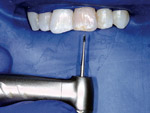

Fig. 14 Isolating a sextant of teeth instead of a single tooth is advantageous for accessing the calcified tooth.

Figure 14